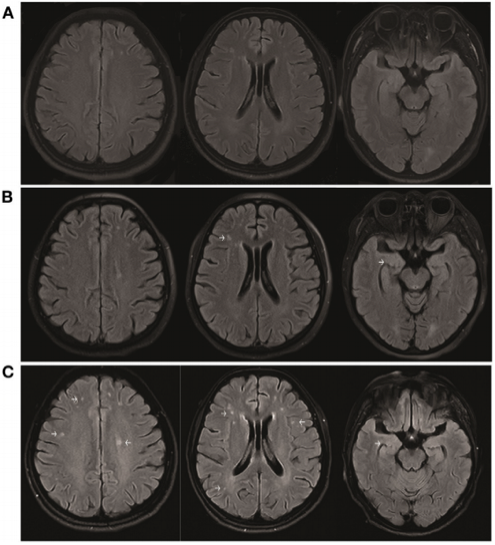

患者在发病后第10天开始接受高剂量类固醇治疗,随后剂量逐渐减少(图1)。1个月后,她的认知功能(简易精神状态检查和蒙特利尔认知评估的总分分别为5分和3分)和运动障碍得到部分改善。未观察到异常行为,尽管患者仍表现出语言障碍、癫痫、肌张力障碍和自主神经功能障碍。脑磁共振成像(MRI)显示,与发病后6天(图3A)相比,发病后17天(图3B)和45天(图3C)皮质下白质和内侧颞叶的分散液体衰减反转恢复(FLAIR)高强度增加。此外,重复CSF分析显示抗NMDA受体抗体(1:3.2)为阳性,但抗AMPA1和抗AMPA2受体抗体为阴性。此后,给予2 g/kg静脉注射免疫球蛋白(IVIg)5天、类固醇和二线药物(霉酚酸酯)的联合治疗。在最后一次随访中,患者认知功能得到改善(简易精神状态检查总分和蒙特利尔认知评估总分分别为18分和11分),未发现异常精神症状、肌张力障碍、癫痫发作和自主神经功能障碍。患者的mRS评分为2分。在30周的随访期间,患者没有复发。

图3. 与发病后6天(A)相比,发病后17天(B)和45天(C)的脑MRI显示皮质下白质和内侧颞叶的分散液体衰减反转恢复高强度增加